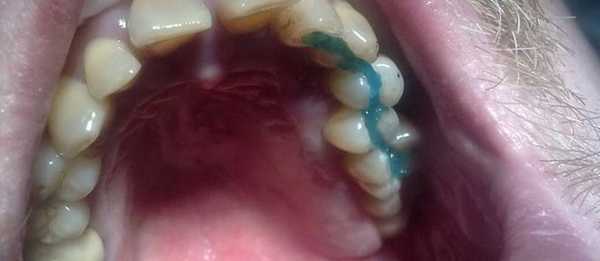

2) Вантовое шинирование. Технологически данный метод очень схожий со стекловолоконным. Только для фиксации используется арамидная нить, отличающаяся прочностью, долговечностью, совместимостью с эмалью зубов и отсутствием реакции на пищу или слюну. Процедуру проводят по такой же схеме, что и со стекловолокном. Арамидную ленту укладывают в горизонтальную бороздку и заливают световым композитом. Вантовая технология шинирования имеет те же преимущества, что и стекловолоконная, но считается более физиологичным способом фиксации.

Вантовое шинирование подвижных зубов

Технология проведения вантового шинирования схожа со стекловолоконным методом. Главное отличие заключается в том, что в данном случае применяется арамидная нить. Это прочное и долговечное волокно, которое совместимо с зубной эмалью и не имеет реакции на такие раздражители, как слюна или пища. Вантовое шинирование обладает всеми преимуществами стекловолоконного, но при этом оно считается более физиологичным вариантом и может заменить протезирование.

Винтовой способ

Основной материал при таком шинировании - армидная нить. Можно использовать такой способ в том случае, когда человек получил травму.

Шинирование зубов при переломе челюстей, усиленной подвижности, позволяет получить заметные результаты.

Процесс установки аналогичен тому, что уже было описано выше. Сначала проводится очистка эмали, потом создается борозда. В углублении натягивается шнур из армидной нити.